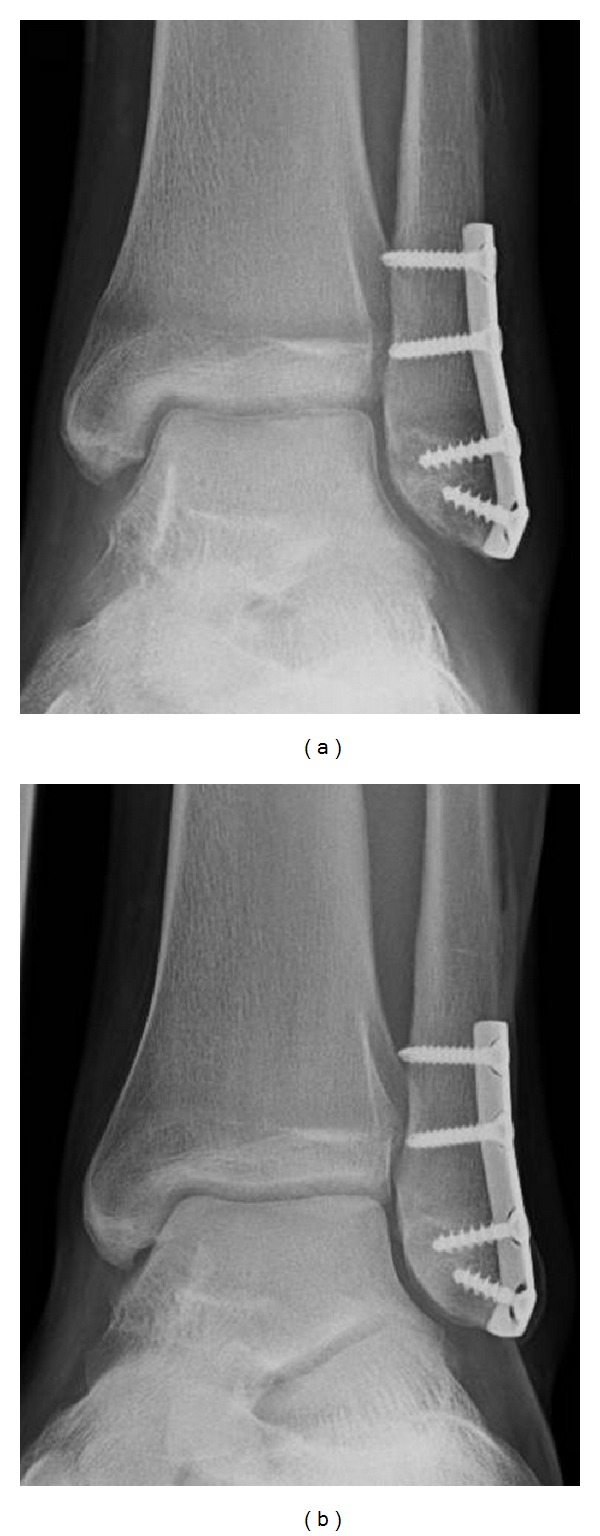

Case 4. A 17 year old young man with a fracture of the distal fibula was treated with osteosynthesis. With immobility subchondral osteopenia of the talus as well as the distal tibial epiphysis could be found. The clinical course was unremarkable. On follow up 8 months later after resumption of normal activity the subchondral osteopenia disappeared (Figure 5).

Figure 5.

Serial radiographs of the left ankle after osteosynthesis of a distal fibula fracture. With immobility subchondral osteopenia of the talus as well as the distal tibial, epiphysis could be found (a) which disappeared after the resumption of normal activity (b).